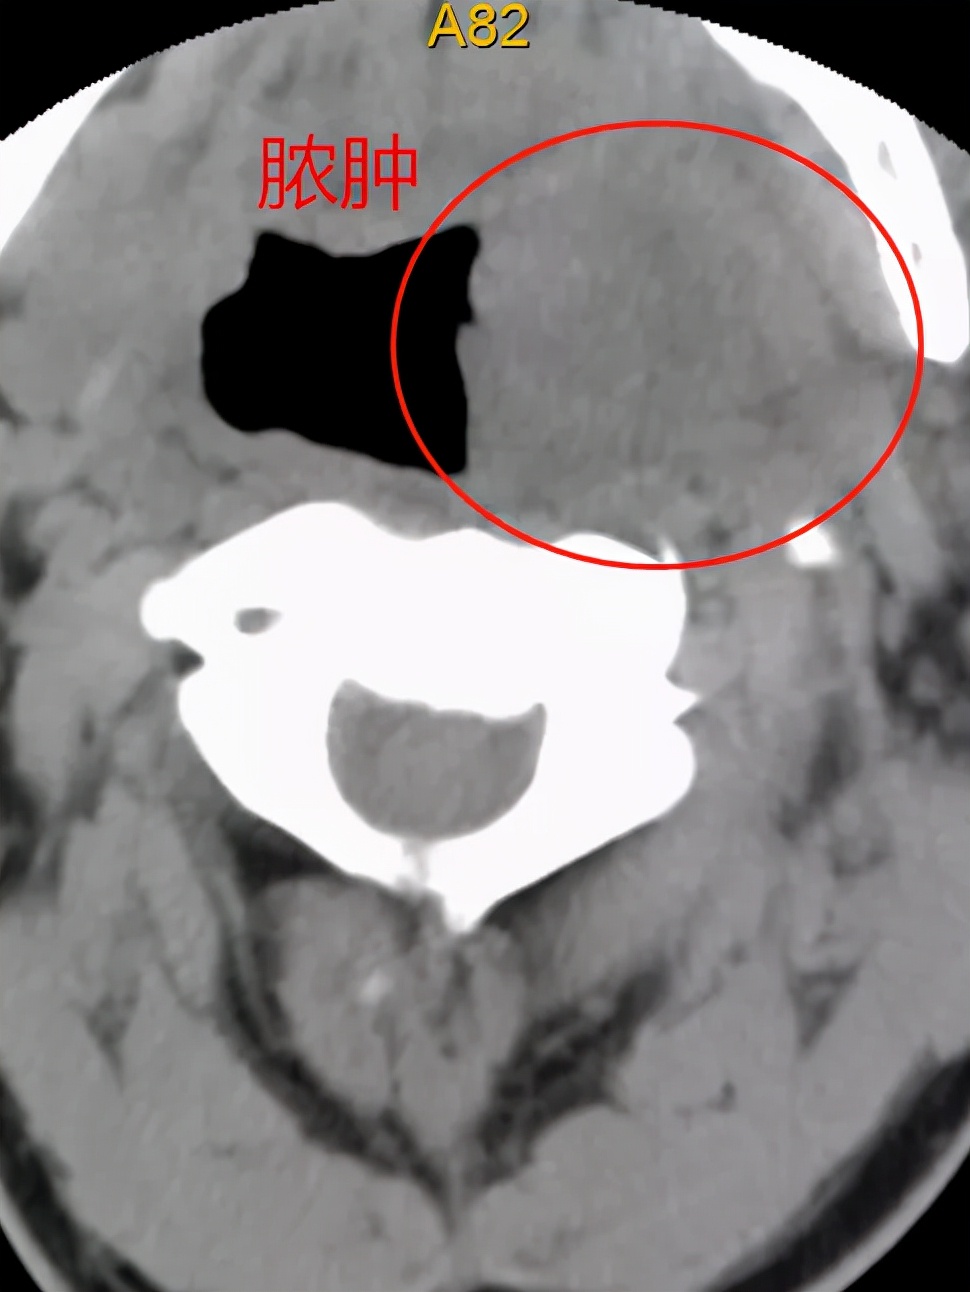

详细询问病史后,张先生由龙华区人民医院耳鼻喉科转入脊柱外科进一步治疗。进一步完善检查和诊断后,摆在医生面前的问题是该患者的手术方案的抉择。 患者咽旁脓肿范围较广,可能累及颈前筋膜,甚至到伤椎的位置。如果冒然进行前路手术,有可能导致感染进一步扩散,甚至导致手术部位感染,后果将不堪设想 。

此外,该患者颈6椎体前中柱骨折,后方结构尚稳定,如果行传统后入路,破坏附着的肌肉群,可能破坏原有的稳定性,同时术后可能存在颈部轴性痛的症状等。脊柱外科主任张昊与全科室医生进行充分讨论,查阅相关文献,与患者充分沟通病情和诊疗计划。与此同时,继续加强患者抗感染治疗,控制脓肿进一步恶化;给患者进行颅骨牵引,评估颈椎曲度改变情况,发现在颅骨牵引后患者颈椎骨折可部分复位,同时颈椎曲度也较前有恢复,最后决定为患者进行 “颈后路肌间隙入路颈椎骨折复位、后凸畸形矫正、钉棒系统内固定、植骨融合术”。该技术具有手术创伤小,术中保留了绝大部分肌群、出血较少,术后患者无明显颈部轴性疼痛的症状等优点,最后患者满意出院。